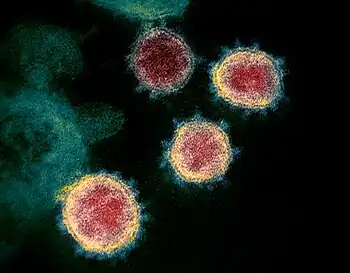

Selected image –

Photo credit: Public domain (U.S. Brookhaven National Laboratory)